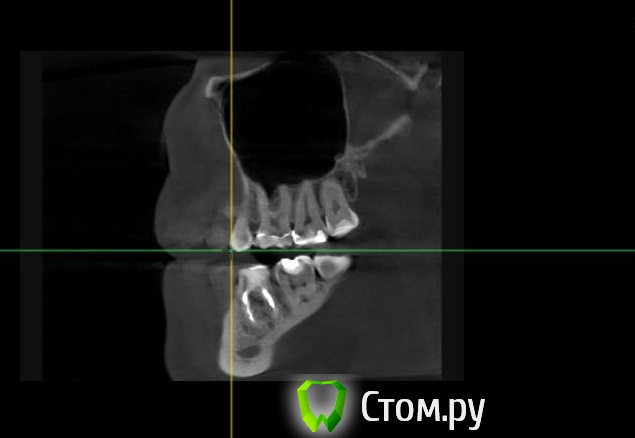

Майло Опубликовано 18 марта, 2014 Автор Поделиться Опубликовано 18 марта, 2014 (изменено) Здравствуйте, наконец сделала кт. Сегодня появилась небольшая боль над правой бровью (после лазера прошла, к вечеру появилась опять). Насморк и заложенность присутствуют. Еще сегодня опять поговорила со своим хирургом имплантологом. По симптомам сказал, что похоже присоединилась какая-то лор болячка и наверное надо сходить к лору. По кт сказал, что все нормально. Немного сужена пазуха справа, но учитывая, что я аллергичная, это нормально. Про капли типа Полидекса, сказал спросить у лора. Завтра я делаю последний лазер, по прежнему промываю нос Отривином Бэби (мне так удобней), пью кларитин, "выбиваю" нос по необходимости, но стараюсь пореже (2-3 раза в день). Еще он отдал кт через 2 недели после имплантации, на всякий случай прикреплю и этот снимок. Самый первый снимок кт был сделан через 2 недели после имплантации. Второй и третий сегодня. Подскажите, я так понимаю данное кт не показывает есть ли у меня гайморит? (к лору смогла записаться аж на 26-е) И все равно хотелось бы узнать ваше мнение по поводу состояния имплантов, есть ли там воспаление или "нагноение"? Изменено 18 марта, 2014 пользователем Майло Ссылка на комментарий

Майло Опубликовано 18 марта, 2014 Автор Поделиться Опубликовано 18 марта, 2014 (изменено) Решила еще добавить пару кадров своих пазух, вначале показалось что справа что-то есть (рис1), потом поняла это костный материал и импланты (рис2). Надеюсь так должно быть. И еще вопрос, может и "тупой", такое яркое свечение имплантов, особенно заметно на фото в профиль, это нормально? Изменено 18 марта, 2014 пользователем Майло Ссылка на комментарий

Bier Опубликовано 18 марта, 2014 Поделиться Опубликовано 18 марта, 2014 выглядит все неплохо, и пазуха чистая. Гайморита у вас нет. Сходите к ЛОРУ 2 Ссылка на комментарий

Майло Опубликовано 19 марта, 2014 Автор Поделиться Опубликовано 19 марта, 2014 (изменено) выглядит все неплохо, и пазуха чистая. Гайморита у вас нет. Сходите к ЛОРУСпасибо. А такие затемнения вокруг имплатов, это нормально? Изменено 19 марта, 2014 пользователем Майло Ссылка на комментарий

red_butler Опубликовано 19 марта, 2014 Поделиться Опубликовано 19 марта, 2014 Да, это артефакты вызванные металлом Ссылка на комментарий